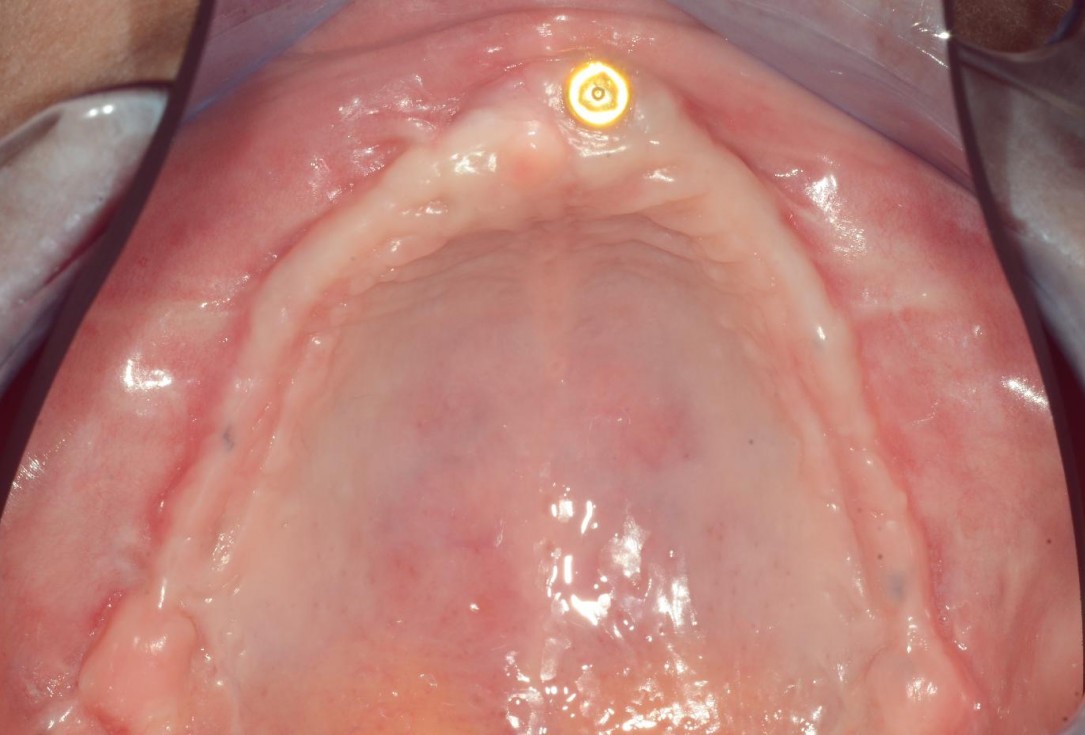

1/8 - Insufficient keratinized mucosa and extremely shallow vestibule on the maxillamucoderm® for full arch reconstruction of insufficient vestibular depth and lack of keratinized tissues - Dr. B. Mólnar & Prof. P. Windisch

Insufficient keratinized mucosa and extremely shallow vestibule on the maxilla